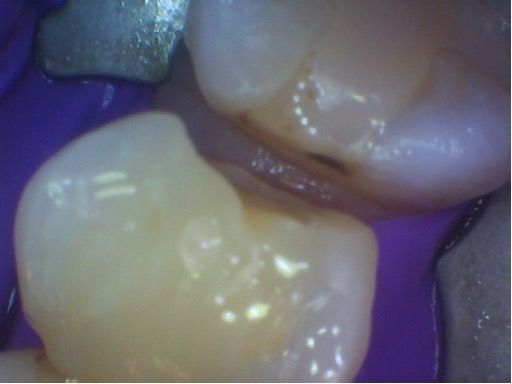

The show case was diagnosed with help of x-rays, where tooth decay started between the teeth and spread . After treatment , the teeth were restored (filled with resin material ) to the natural shape with access to the floss to help prevent new lesions from occurring .